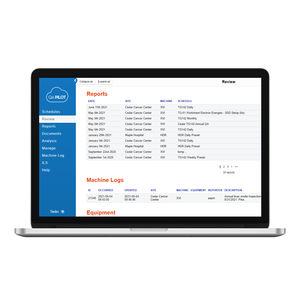

módulo de software de monitorización de dosis de radiaciónQA Pilot™

... calidad, integre los resultados y gestione los dispositivos desde una plataforma estándar Cuadros de mando Cada área del software comienza con una visión general del tablero de control filtrable, personalizada según ...